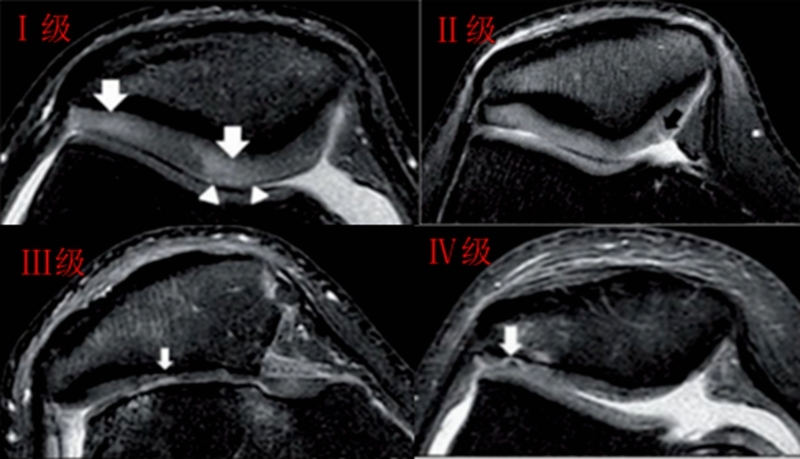

髌骨软骨软化分级表现

Ⅰ级:关节软骨失去珍珠样外观而变得较暗淡,局部软化,肿胀区或纤毛化区的直径<0.5cm。

Ⅱ级:关节软骨软化区内出现毛刷状或纤毛化改变,深达1-2mm,直径≤1.3cm。

Ⅲ级:软骨的毛刷状或纤毛化改变达关节软骨厚度一半以上,直径>1.3cm,关节软骨表面类似蟹肉样改变,表面有多发软骨碎片附着其下的软骨。

Ⅳ级:关节软骨全层受侵,软骨下骨暴露,表现为进展期髌股关节炎。